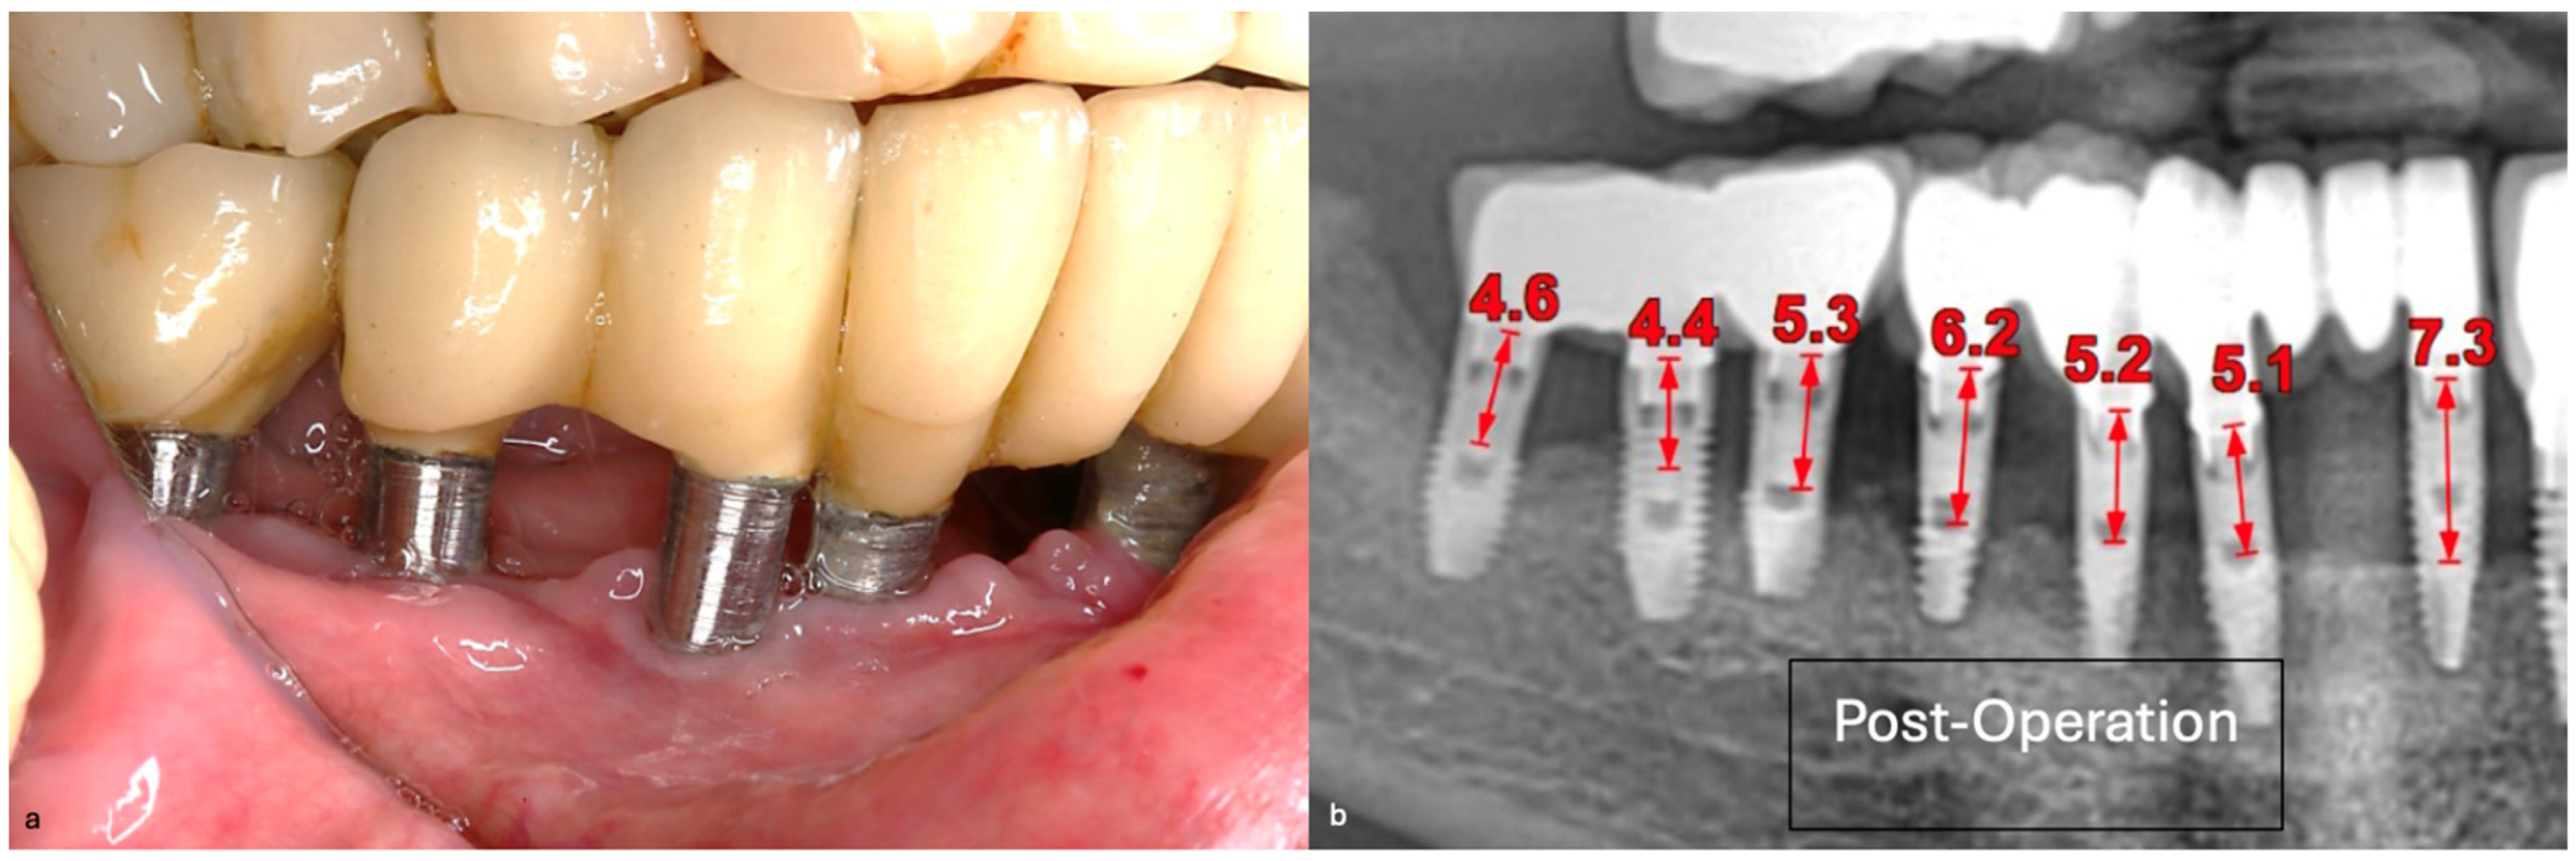

The intraoral examination revealed poor oral hygiene, characterized by significant plaque accumulation (over 65% plaque index) along the gingival margins and interdental areas. The periodontal status evidenced a progressive periodontal disease, with bleeding on probing (BoP) over 60%, mainly around all dental implants; peri-implant tissues possessed a high level of inflammatory condition, with localized swelling, high level of BoP, redness, and suppuration at the site of teeth #46 and #47, indicating local acute inflammation. The probing depth (PD) at site implant #46 exceeded 9 mm at both the mesial and distal sites, and at #47, the mesial site had a PD of 7.8mm, while the distal site showed lower bone loss (Figure 7).

Radiographically (Figure 8), the findings demonstrated full mouth edentulism, rehabilitated with upper and lower bridges and crowns supported by dental implants, as well as bone loss at #37, #46, and #47. The peri-apical radiograph (Figure 7) showed two dental implants, each measuring 13 mm, with bone loss around implant #46 (exceeding 60% of the implant length) and around implant #47 (exceeding 70% of the implant length).

Figure 7. The periapical image taken for #46 and #47 (region of the complaint) shows relevant bone loss around the implants (red arrows showing the bone loss found, considering as reference the implant platform).

Figure 14. Periapical images showing the evolution of the case (red arrows show the distance from the implant platform to the bone—(A) Baseline; (B) After 14 months; (C) After 43 months).